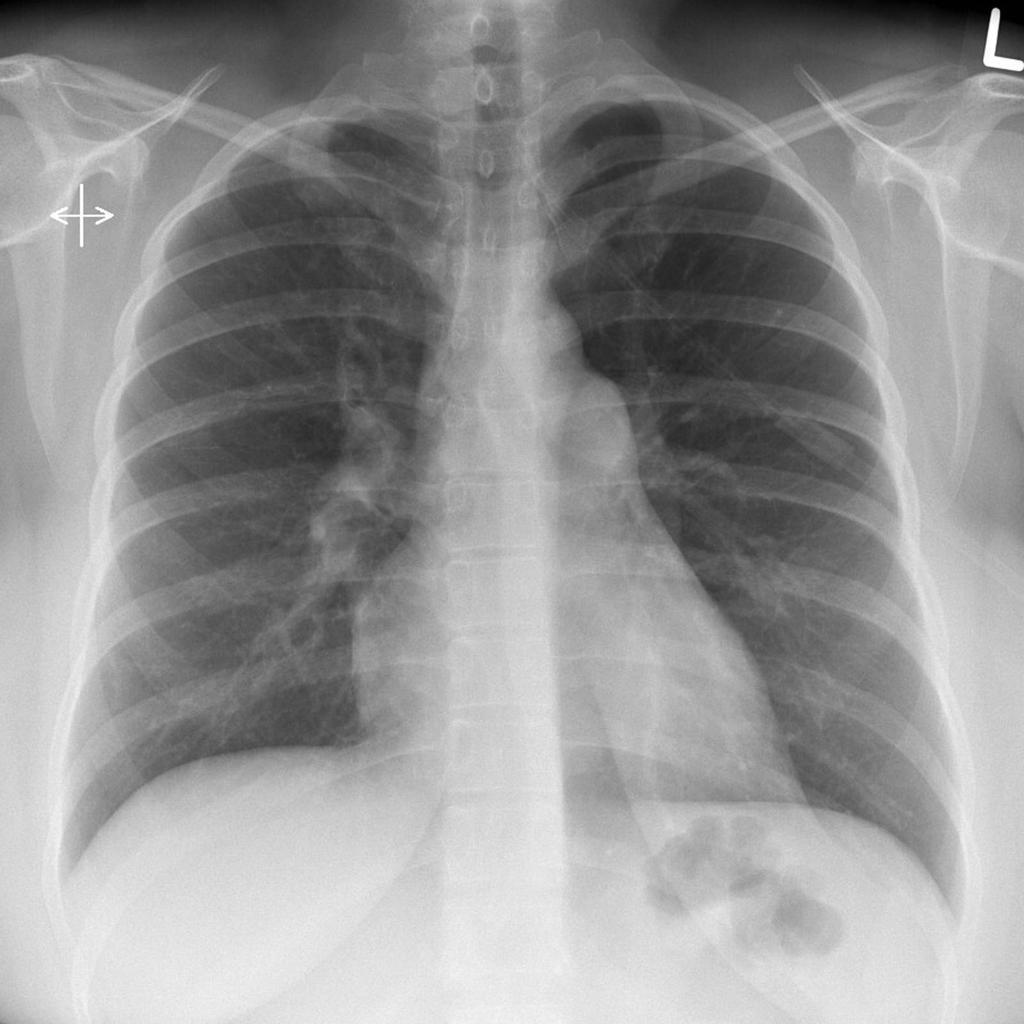

Heart borders on a CXR

How to identify pulmonary trunk on CXR?

ABove the left main bronchus but below the aortic knuckle